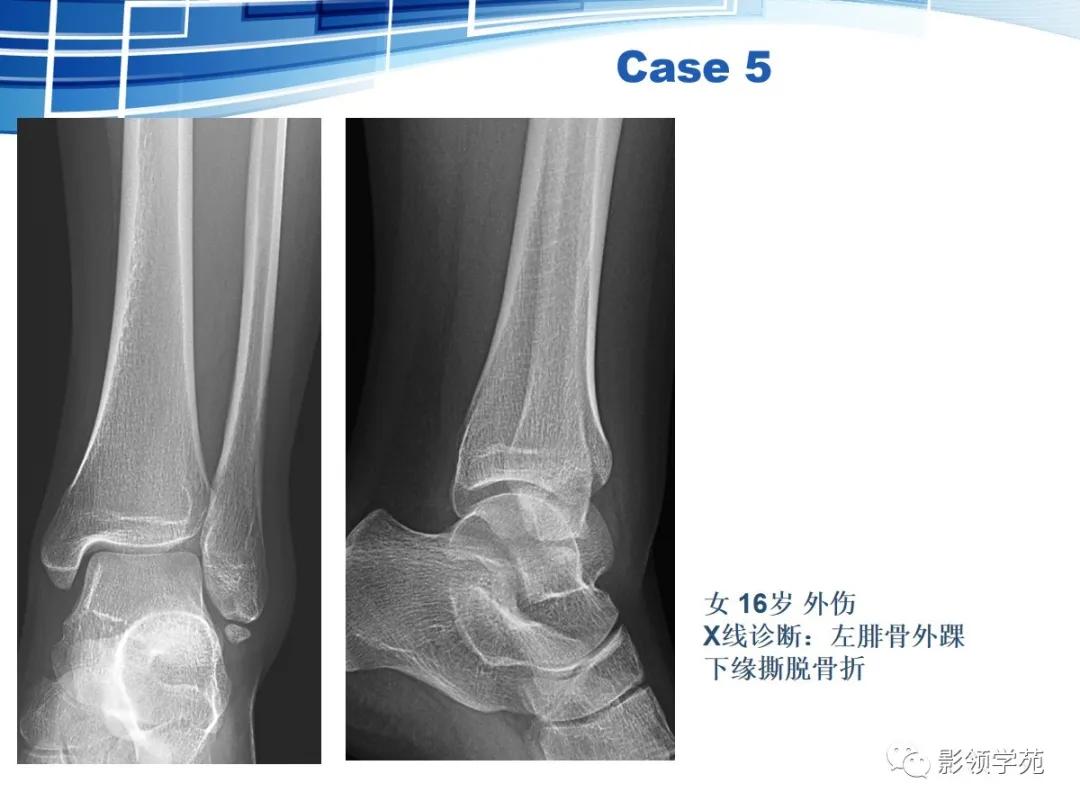

撕脱性骨折的影像学特征

具有典型的好发部位,如肱二头肌肌腱附着处撕脱引起的肱骨大结节撕脱骨折。

具有骨折的直接、间接征象,例如撕脱后的游离骨及所对应的受损骨,其骨皮质不连续或缺损,且其边缘锐利、清晰(CT更能清楚显示);MRI可示局部软组织肿胀、积液或积血等改变;最有利的证据是伤后一段时间,上述征象发生了如边缘骨质吸收、有骨硬化、骨痂生长、局部软组织肿胀消退等动态改变。

撕脱骨块脱离后位移方向与其损伤机制密切相关。

撕脱性骨折多病情急、病程比较短。

鉴别要点:

虽然撕脱性骨折与永存骨骺、籽骨和副骨在影像学上均有游离的小骨块影的表现,但前者具有骨折的影像学一般特征,而后三者不具有。

永存骨骺、籽骨和副骨的发生与其特有部位及典型特征紧密联系。

常见案例均具有骨块边缘钝圆、骨皮质连续、局部软组织无明显肿胀以及伤后该骨的连续摄片无明显变化等非撕脱性骨折的共同特点。

鉴别重点:独立的骨结构(游离骨)若与相对骨的缺损缘相吻合,是撕脱,如有外伤,更支持。